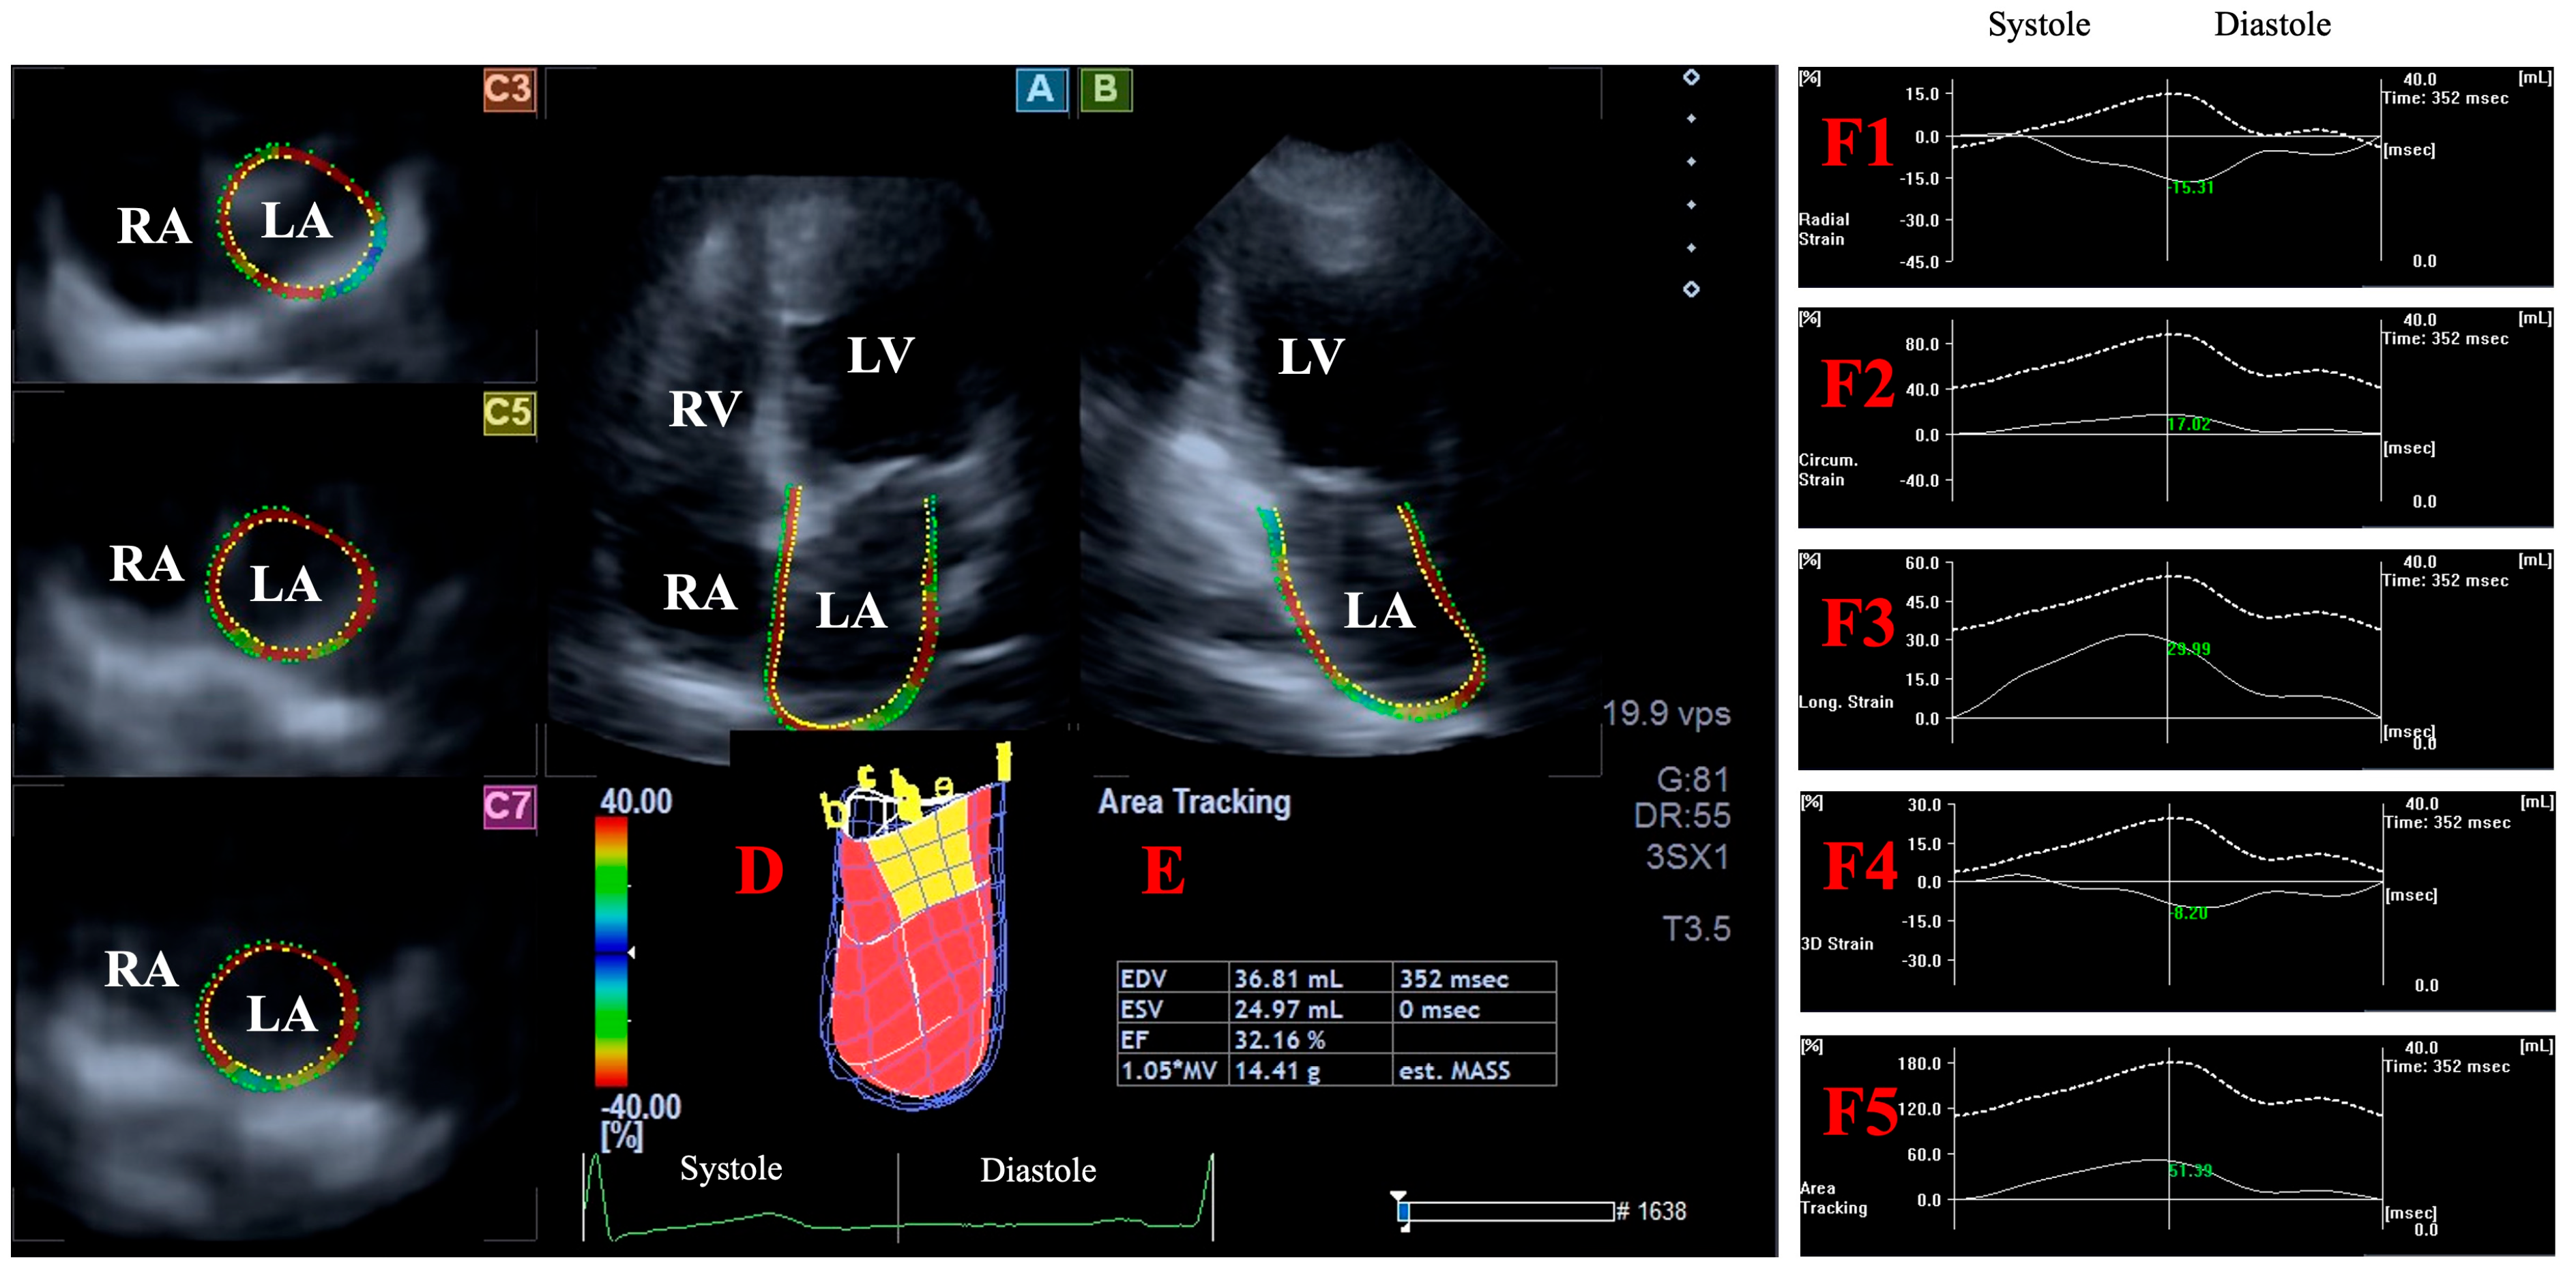

2.3. Three-Dimensional Speckle-Tracking Echocardiography--Derived Data Acquisition

2.4. Three-Dimensional Speckle-Tracking Echocardiography-Derived LV Volumetric Measurements

2.5. Three-Dimensional Speckle-Tracking Echocardiography-Derived Assessment of Peak LA Global Strains

- LA-Vmax—maximum LA volume at end-systole;

- LA-VpreA—pre-atrial contraction LA volume at early diastole;

- LA-Vmin—minimum LA volume at end-diastole;

- LA-GRS—LA global radial strain representing LA thinning/thickening;

- LA-GCS—LA global circumferential strain representing LA widening/narrowing;

- LA-GLS—LA global longitudinal strain representing LA lengthening/shortening;

- LA-G3DS—LA global 3D strain, combination of all unidirectional LA strains;

- LA-GAS—LA global area strain, combination of LA circumferential and longitudinal strains.